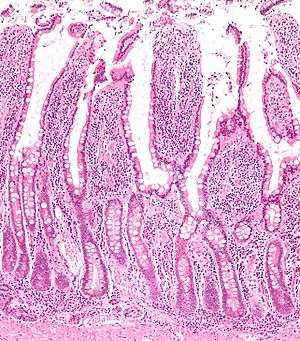

Histology

The three sections of the small intestine look similar to each other at a microscopic level, but there are some important differences. The parts of the intestine are as follows:

Digested food is now able to pass into the blood vessels in the wall of the intestine through either diffusion or active transport. The small intestine is the site where most of the nutrients from ingested food are absorbed. The inner wall, or mucosa, of the small intestine is lined with simple columnar epithelial tissue. Structurally, the mucosa is covered in wrinkles or folds called plicae circulares, which are considered permanent features in the wall of the organ. They are distinct from rugae which are considered non-permanent or temporary allowing for distention and contraction. From the plicae circulares project microscopic finger-like pieces of tissue called villi (Latin for "shaggy hair"). The individual epithelial cells also have finger-like projections known as microvilli. The functions of the plicae circulares, the villi, and the microvilli are to increase the amount of surface area available for the absorption of nutrients, and to limit the loss of said nutrients to intestinal fauna.